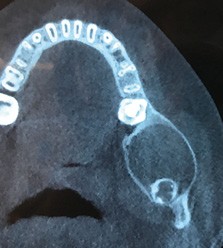

Les kystes et tumeurs bénignes osseuses maxillaires ou mandibulaires chez l’enfant sont le plus souvent asymptomatiques. Ces lésions osseuses sont découvertes de façon fortuite lors d’un bilan radiographique de routine réalisé par l’odontologiste pédiatrique ou l’orthodontiste [1-3]. Néanmoins, des lésions peuvent parfois se développer rapidement et être destructrices [1, 2]. Certains signes cliniques spécifiques à la chronologie de l’éruption dentaire chez l’enfant doivent nous alerter tels qu’un retard d’éruption dentaire ou une éruption dentaire asymétrique (fig. 1). D’autres manifestations cliniques, moins spécifiques à l’enfant, peuvent également orienter le clinicien sur la présence d’une pathologie osseuse sous-jacente : mobilité dentaire, douleur, tuméfaction, limitation de l’ouverture buccale, trouble neurosensoriel, etc. [3]. C’est la radiographie panoramique qui va ensuite mettre en évidence/confirmer la présence d’une lésion intra-osseuse (fig. 2).